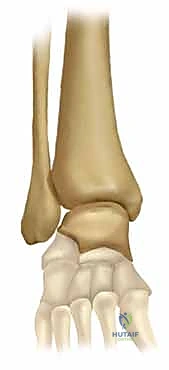

يتكون مفصل الكاحل من التقاء ثلاث عظام رئيسية:

1. عظمة الظنبوب (Tibia): وهي العظمة الأكبر في الساق، ونهايتها السفلية تشكل ما يُعرف بـ "الكعب الإنسي" (Medial Malleolus) وهو البروز العظمي الداخلي للكاحل.

2. عظمة الشظية (Fibula): وهي العظمة الأصغر في الساق، ونهايتها السفلية تشكل "الكعب الوحشي" (Lateral Malleolus) وهو البروز العظمي الخارجي.

3. عظمة الكاحل (Talus): وهي العظمة التي ترتكز عليها الساق وتعمل كحلقة وصل مع باقي عظام القدم.